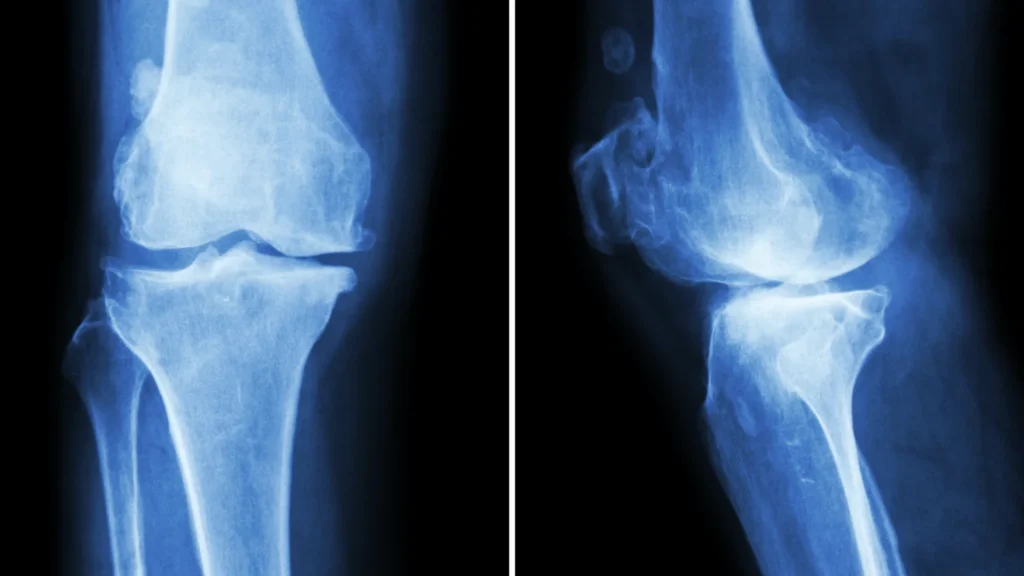

Osteoarthritis isn’t just about cartilage wearing down. It’s an active biological process where the synovium (the joint lining) becomes inflamed.

Researchers from University College London and the Cleveland Clinic have shown that the release of pro-inflammatory molecules — especially interleukin-6 and TNF-alpha — accelerates cartilage breakdown. This inflammation increases joint fluid and swelling, putting pressure on nerves and reducing the smooth glide of movement.

In short, the joint’s delicate ecosystem — cartilage, bone, synovial fluid — goes out of balance. The joint’s cartilage loses elasticity, and bone spurs may start forming as the body’s way of compensating. Ironically, these little “repairs” can cause even more friction.

B. Swelling and Warmth in Joints

When the joint’s cartilage becomes irritated, your body floods the area with synovial fluid to cushion the impact. That’s why joints may look puffy or feel warm to the touch. It’s the inflammation doing its job — just a bit too enthusiastically.

Warm compresses and light massage may help ease that tight, full feeling. Doctors sometimes confirm inflammation through joint fluid analysis or MRI scans if it persists.

- X-rays or MRI scans for cartilage and bone changes.